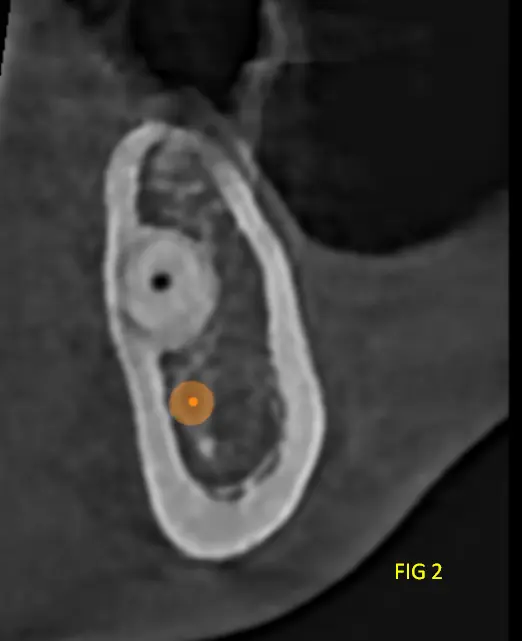

En cortes transversales se aprecia la naturaleza infiltrativa de la lesión, con forma de rayos de luz, sin límites netos, característica típica del mixoma Odontogénico.